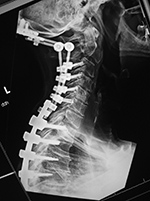

| 59 year-old man with past history of C3-5 fractures and extensive posterior spinal fixation from the occiput to T8. Lateral radiographs of the cervical spine three months apart show dislodgement (arrow) of the bilateral cervical posterior rods from connection with the thoracic rods at the C7-T1 level. Left: before dislodgement. Right: after dislodgement. After dislodgement there is increased kyphosis at the C6-7 level. |

From Hunter, 2004 |